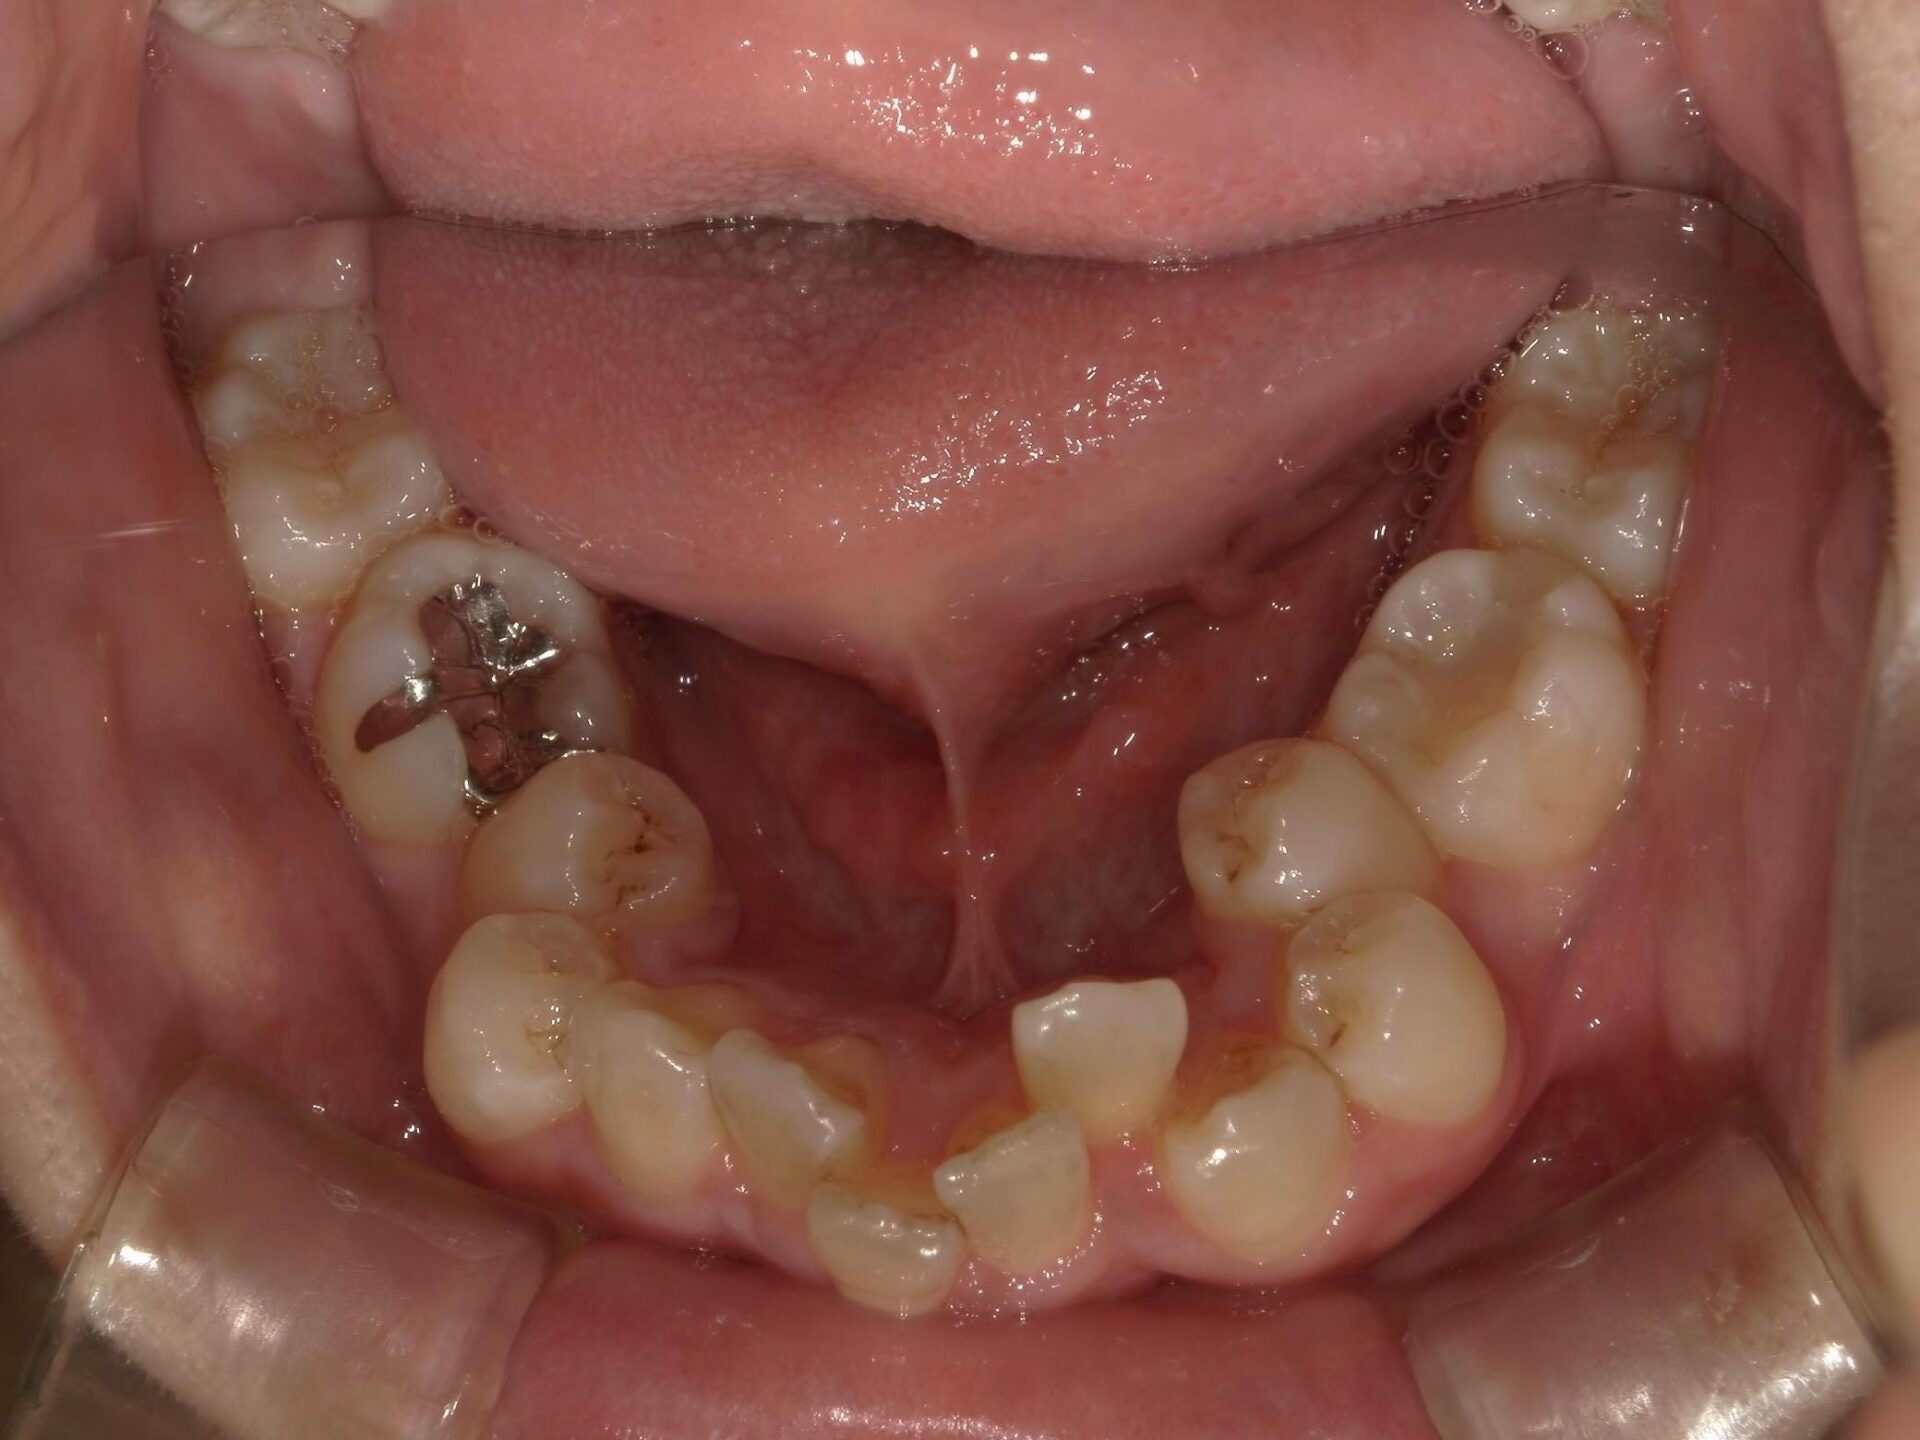

10代、女性、ワイヤー

| 施術内容 | 主訴:上下前歯でこぼこ。なるべく抜きたくない。 詳細:ワイヤー矯正での歯並び改善 詳細:ワイヤー矯正での歯並び改善 歯肉炎リスクあるため、今後は後戻りのチェックとともに歯肉炎管理もしていきます。 |

| 治療期間 | 12ヶ月(2/6現在 治療終了) |

| リスク・副作用 | ■リスク・副作用 ・治療の初期段階では、痛みや不快感が生じやすくなりますが、一週間前後で慣れます。 ・歯の動き方には個人差があるため、予想された治療期間より延長する場合があります。 |

| 費用 | ワイヤー矯正 60万円(税込660,000円) |